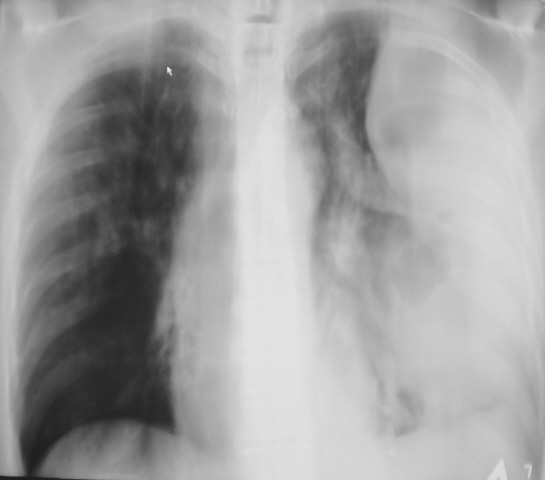

Иллюстрация 2. Слева определяется субтотальное снижение прозрачности легочного поля за счет наличия значительных размеров паракостального осумкованного выпота, имеющего чёткий и ровный контур. На фоне инфильтративно измененной легочной ткани в верхнем, среднем и нижнем легочных полях четко определяются две структуры — просветления с горизонтальными уровнями жидкости. Слева купол диафрагмы подтянут, фиксирован. Тень средостения резко смещена вправо.